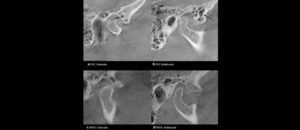

El objetivo del presente estudio fue evaluar los factores (referidos a la CBCT) que influyen en la toma de decisión en tratamientos para extracción de